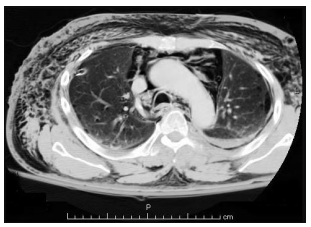

Homem de 18 anos, vítima de colisão moto x auto há 2 horas, refere apenas muita dor torácica para respirar, estando estável hemodinamicamente. Exame físico direcionado: enfisema de tecido celular subcutâneo principalmente em região anterior e lateral do tórax, expansibilidade simétrica bilateralmente, murmúrio vesicular presente bilateralmente, sem alteração à percussão. A TC de tórax é apresentada a seguir:

Assinale a alternativa correta em relação ao diagnóstico e a conduta adequada nesse caso.